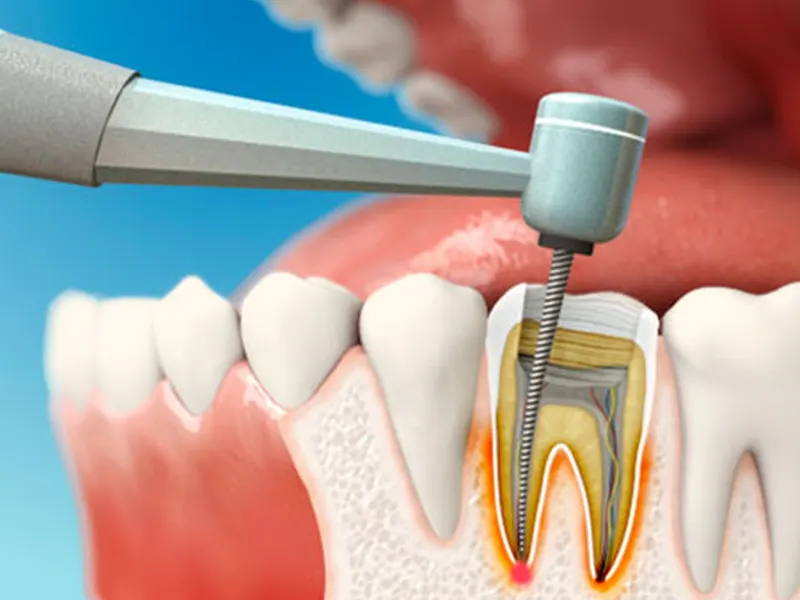

جراحی ریشه دندان یا درمان ریشه دندان، به فرآیند درمان مشکلاتی گفته میشود که در قسمت داخلی دندان (پالپ) اتفاق میافتد. زمانی که پالپ دندان عفونی یا آسیب میبیند، ممکن است نیاز به درمان ریشه داشته باشید. در این حالت، متخصص جراحی ریشه در کرمانشاه با استفاده از تکنیکهای پیشرفته دندانپزشکی، فرآیند درمان را به طور دقیق و حرفهای انجام میدهد.

جراحی ریشه معمولاً زمانی توصیه میشود که درمانهای سادهتری مانند پر کردن دندان نتواستهاند مشکل را حل کنند. در این صورت، متخصص جراحی ریشه با حذف پالپ آسیب دیده، عفونت را از بین میبرد و دندان را به حالت طبیعی خود بر میگرداند.

در ابتدا، پزشک با استفاده از رادیوگرافی دقیق، وضعیت دندان و عفونتهای موجود در ریشه را بررسی میکند. سپس درمان آغاز میشود. ابتدا متخصص جراحی ریشه در کرمانشاه ناحیه درمان را بیحس میکند تا بیمار هیچ دردی در طول جراحی احساس نکند. بعد از آن، دکتر معصومه دولتیاری با استفاده از ابزارهای تخصصی، پالپ آسیب دیده را از دندان خارج میکند و تمامی کانالهای ریشه را تمیز میکند.

در مرحله بعد، ریشه دندان به طور کامل پر میشود تا از هرگونه عفونت مجدد جلوگیری شود. در نهایت، دندان با مواد خاصی پر شده و اگر لازم باشد، روکش بر روی آن قرار میگیرد تا از دندان محافظت شود.